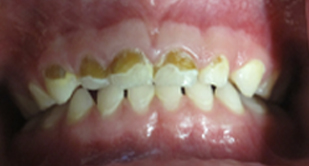

Fluoride

Fluoride is a naturally occurring element, which has shown to prevent tooth decay by as much as 50-70%, Despite the advantages, too little or too much fluoride can be detrimental to the teeth. With little or no fluoride, the teeth aren’t strengthened to help them resist cavities. Excessive fluoride ingestion by young children can lead to dental fluorosis, which is typically a chalky white discoloration (brown in advanced cases) of the permanent teeth. Be sure to follow your pediatric dentist’s instructions on suggested fluoride use and possible supplements, if needed.

You can help by using a fluoride toothpaste and only a smear of toothpaste (the size of a grain of rice) to brush the teeth of a child less than 3 years of age. For children 3 to 6 years old, use a "pea-size" amount of toothpaste and perform or assist your child’s toothbrushing. Remember that young children do not have the ability to brush their teeth effectively on their own. Children should spit out and not swallow excess toothpaste after brushing, in order to avoid fluorosis.